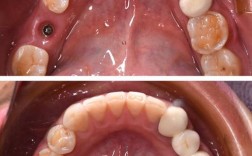

种植牙是目前修复缺失牙的有效方式,但并非所有人都能直接进行种植牙手术,当患者牙槽骨量不足(如骨宽度、高度不够)、骨质量较差时,往往需要先进行植骨手术,为种植体提供足够的骨支持,究竟哪些人需要进行种牙植骨呢?本文将从多个维度详细解析需要植骨的...

长期缺牙通常是可以进行种植牙修复的,但需要根据具体情况评估,并且治疗过程可能会比近期缺牙的情况更复杂、时间更长、费用也可能更高,以下是长期缺牙进行种植牙需要考虑的关键因素和可能遇到的问题:🦴1.牙槽骨吸收与萎缩(最主要的问题)原因:牙...

是的,缺多颗牙通常非常适合种植牙修复,甚至可以说是目前最理想、最接近天然牙的修复方式之一,但是否适合以及具体方案如何,需要经过专业医生的全面评估,以下是关于多颗牙缺失进行种植牙修复的详细分析:✅为什么多颗牙缺失非常适合种植牙?恢复咀嚼功能...